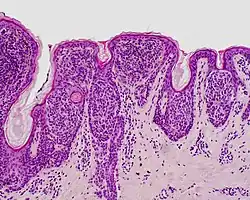

| Junctional nevus | Along the junction of the epidermis and the underlying dermis.[15] | May be colored and slightly raised.[16] |

ICD10: D22 ICDO: M8740/0 |